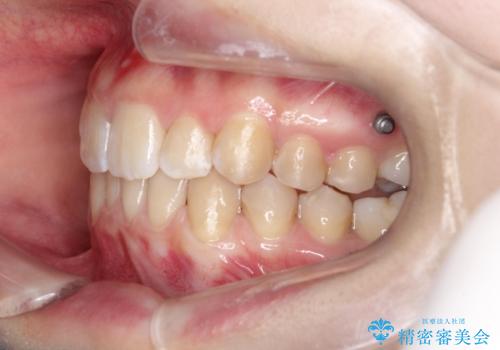

目立たない矯正で歯のデコボコと反対咬合を改善

- 前歯のデコボコ(叢生)と、前歯が上下逆の咬み合わせ(反対咬合)を主訴にご来院されました。精密検査の結果、歯列全体のスペースが不足していることが判明。患者様のご希望に合わせ、透明で目立ちにくい**インビザライン(マウスピース矯正)**による治療計画を立案しました。歯を抜かずに、歯列全体を奥(遠心)へ移動させることで、歯が並ぶスペースを確保し、叢生と反対咬合を同時に改善することを目指します。

今回の矯正治療では、透明なマウスピース型の装置インビザラインを使用しました。この装置は目立たず、取り外しが可能なため、食事や歯磨きも普段通り行えます。治療は、緻密な治療計画に基づき、段階的に作製されたマウスピースを交換していくことで、遠心移動という方法で奥歯から徐々に歯列全体を後方へ動かしました。これにより、不足していたスペースを確保し、前歯のデコボコを解消。同時に、上下の歯の前後的な関係を改善することで、反対咬合も正常な咬み合わせへと導きました。見た目も機能も改善し、自然で美しい笑顔を獲得していただけました。